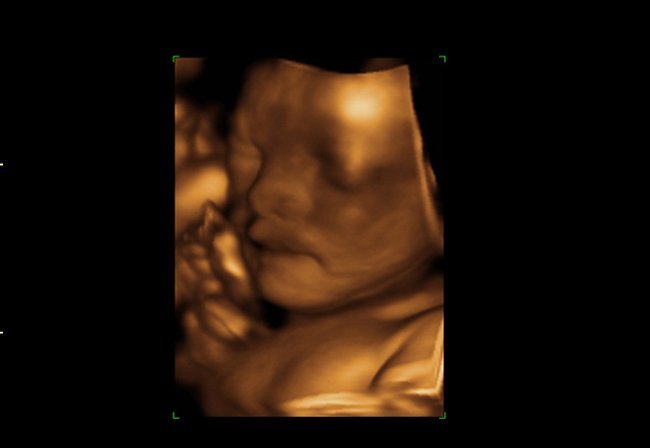

Ecografía 4D

La ecografía 4D (o 3D más movimiento en tiempo real) es una técnica de lo más de moda últimamente. No suplanta la ecografía tradicional, sino que la complementa. Es una ecografía que se realiza a nivel privado, por lo que hay varias cosas a tener en cuenta antes de contratarla.

Desde el punto de vista de detección de anomalías fetales, no aporta un valor añadido a las anteriores a nivel de funcionamiento de órganos, morfología, crecimiento del bebé, etc. Puede ser más valiosa para detectar por ejemplo problemas de la piel o deformidades como el labio leporino o la fisura palatina.

No deja de ser una prueba de diagnóstico prenatal, pero es trascendente más que nada desde elpunto de vista emocional, ya que permite a los padres conocer la carita de su bebé. Las imágenes son bastante nítidas pero no es una foto, sólo permite hacernos una idea de sus rasgos.

Las ecografías 4D pueden realizarse en cualquier momento del embarazo aunque las mejores imágenes se obtienen entre las semanas 24 y 30 pues las condiciones son las más adecuadas. La proporción de líquido amniótico y el tamaño intermedio del bebé permiten visualizarlo mejor.